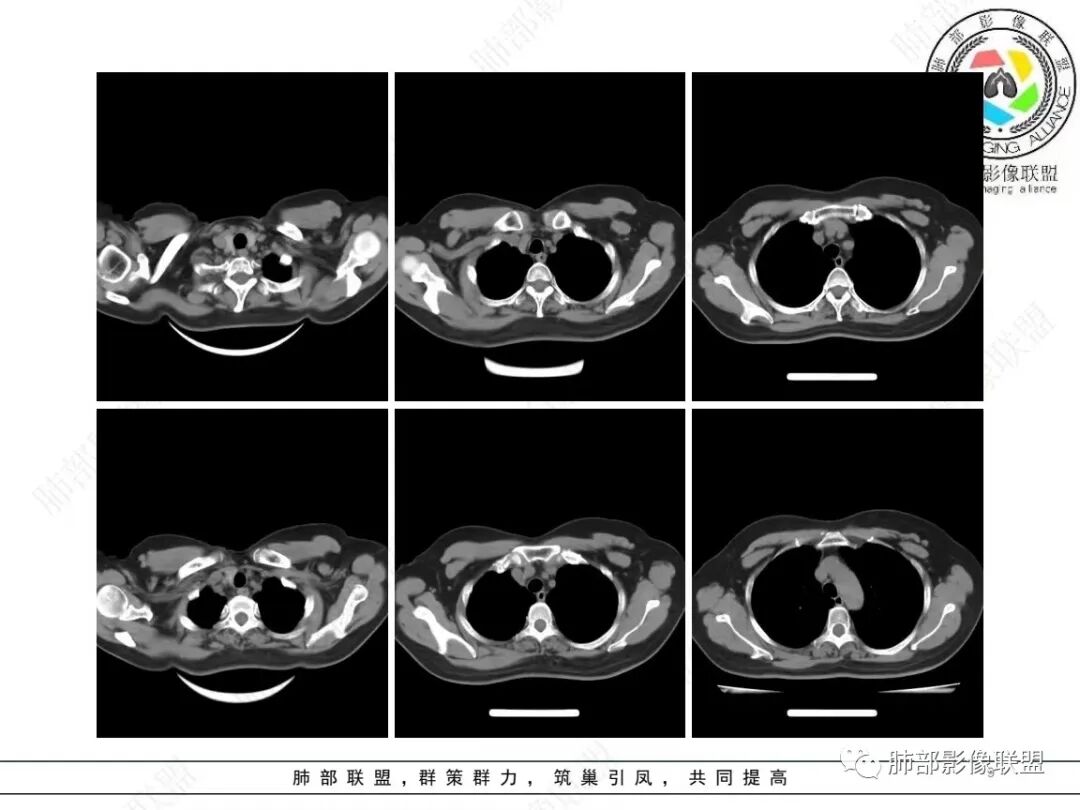

1、临床特点:58岁女性,体检发现右肺结节7天,无基础病,中性粒细胞百分比略高,无实验室检查无特殊。

2、影像特点:右肺下叶胸膜下不规则结节,矢状位整体病灶沿着支气管方向呈斑片状,不均匀强化。病灶边缘多平直、凹陷(从部分层面可见极其像月牙铲),缺乏膨隆感,周围可见多发长索条影,病灶内可见多发充气支气管影,大部分支气管完全贯通病灶并轻度扩张,极少支气管进入病灶内堵塞,观察横断位视频、部分层面病灶周围可见边界欠清的ggo。纵隔窗病灶内未见明显钙化影。未见卫星病灶及树芽征。

3、综合分析:中老年女性胸膜下不规则结节,无特殊临床表现,实验室检查亦无特殊,病灶在部分断面呈斑片状,边缘多平直甚至凹陷,缺乏分叶及膨隆感,未见粗短毛刺及胸膜凹陷,部分层面似见”月牙铲“样外形,但缺乏张力的“月牙铲”不太可靠。灶周磨玻璃晕也会让人警惕肺腺癌可能,磨玻璃影边界是否清晰常须薄层仔细分辨。

实性密度为主结节影,支气管密切相关,边缘多平直,缺乏分叶膨隆感,缺乏张力,有磨玻璃晕但边界不清。更符合慢性炎性病变。